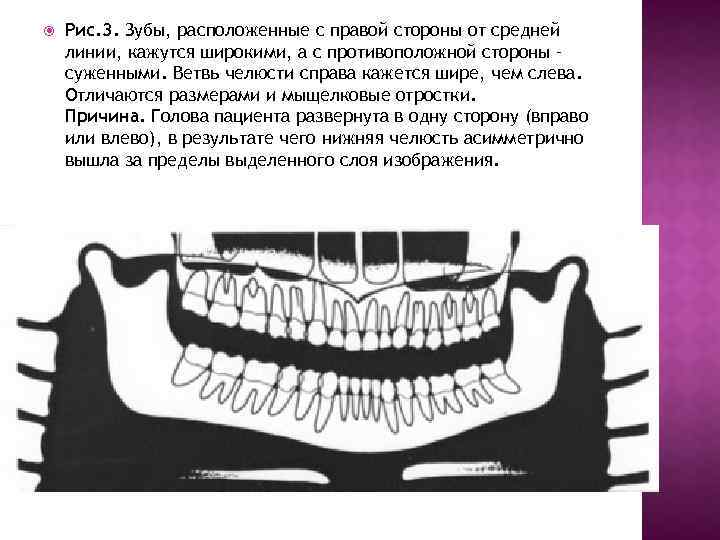

Рис. 3. Зубы, расположенные с правой стороны от средней линии, кажутся широкими, а с противоположной стороны – суженными. Ветвь челюсти справа кажется шире, чем слева. Отличаются размерами и мыщелковые отростки. Причина. Голова пациента развернута в одну сторону (вправо или влево), в результате чего нижняя челюсть асимметрично вышла за пределы выделенного слоя изображения.